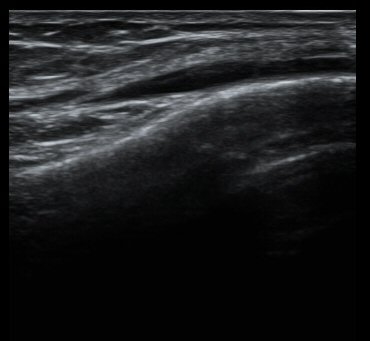

´ëÅð°ñ ¿ÜÃø°ú ¾ÕÂÊ Á¾´Ü¸é°Ë»ç¿¡¼­ ¾à°£ÀÇ ¼ö¾×Àú·ù°¡ °üÂûµÊ(±×¸² 1, 2).